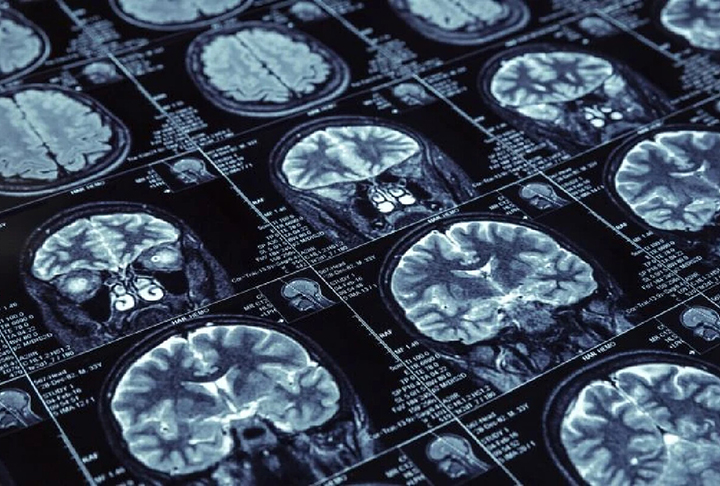

Os exames no jovem identificaram uma atrofia do hipocampo cerebral, além do acúmulo da proteína beta. As duas são características da doença. Também houve um aumento da proteína tau, outra característica. Foto: Reprodução -